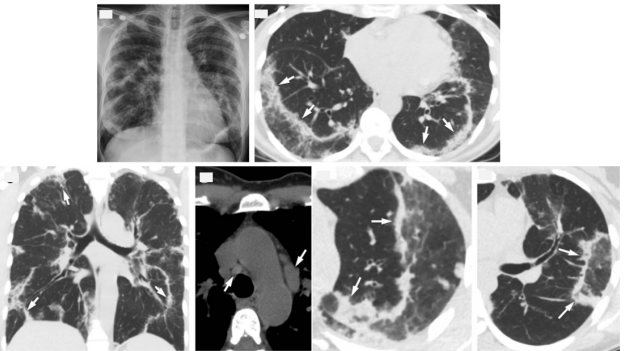

图片

ICEP影像学表现

图源:Radiol Clin North Am, 2016, 54(6):1151-1164. Radiographics, 2007, 27(3):617-37; discussion 637-639.